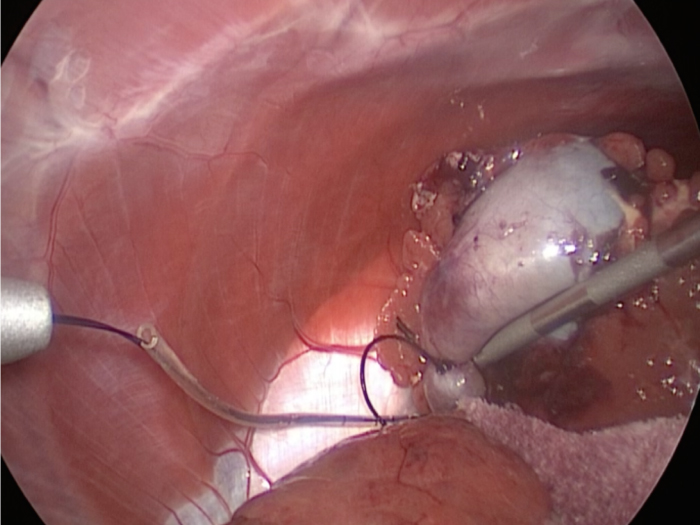

体の外に出すためお腹の中で袋に入れていきます。

回収袋にいれて体外に摘出していきます。

お腹の中を洗浄して終了となります。

回収袋にいれて終わりになります。